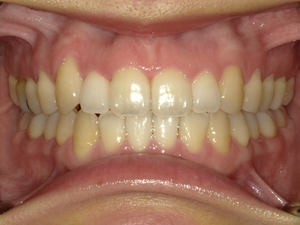

●ご相談内容:歯がガタガタしてる●矯正の種類:マウスピース型矯正「インビザライン」●治療期間:26週間●治療費用:66万円(税込)